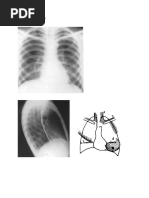

Examenul radiologic

Evidenţiază hipertransparenţa pulmonară, orizontalizarea coastelor cu spaţii

intercostale lărgite, diafragm coborât, cu excursii reduse. în forma de emfizem

CL desenul pulmonar este accentuat şi poate fi prezent în mantia plămânului,

spre deosebire de emfizemul PL unde structura vasculară este mult sărăcită, cu

zone de hipertransparenţa extinse şi absenţa desenului în mantie.

EMFIZEM PULMONAR